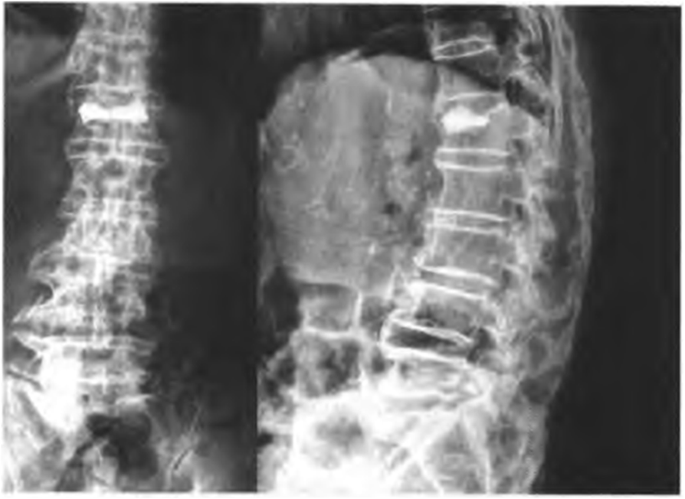

The skin and subcutaneous soft tissue were cut with a scalpel at the marked location, the length of incision is about 0.5 cm. Under fluoroscopy, the core puncture needle was placed into the pedicle (the left pedicle was 10 points outside, and the right pedicle was 2 points outside). Adjust the puncture needle tilt or tail tilt angle according to the fracture line area. Under the lateral fluoroscopy, it is confirmed that the puncture needle is located in the pedicle, and continues to puncture the vertebral body to the posterior one in three of the vertebral body. At this time, the fluoroscopy needle tip is located slightly inside the inner edge of the pedicle shadow. This process requires precise penetration into the fracture line area, then exits the puncture needle, and the hollow drill takes a biopsy. An injection volume of bone cement was 2 to 3 ml per segment in thoracic vertebra and 3 to 4 ml in lumbar, respectively. Stitching incision and covered with a sterile applicator, postoperative prone position for 15 min after surgery to better coagulates bone cement. Preoperative MRI film of L1 OVCF is shown in Fig. 1, the specific steps of the operation are shown in Fig. 2, X-ray film after PVP shows a small amount of bone cement in the OVCF is shown in Fig. 3.